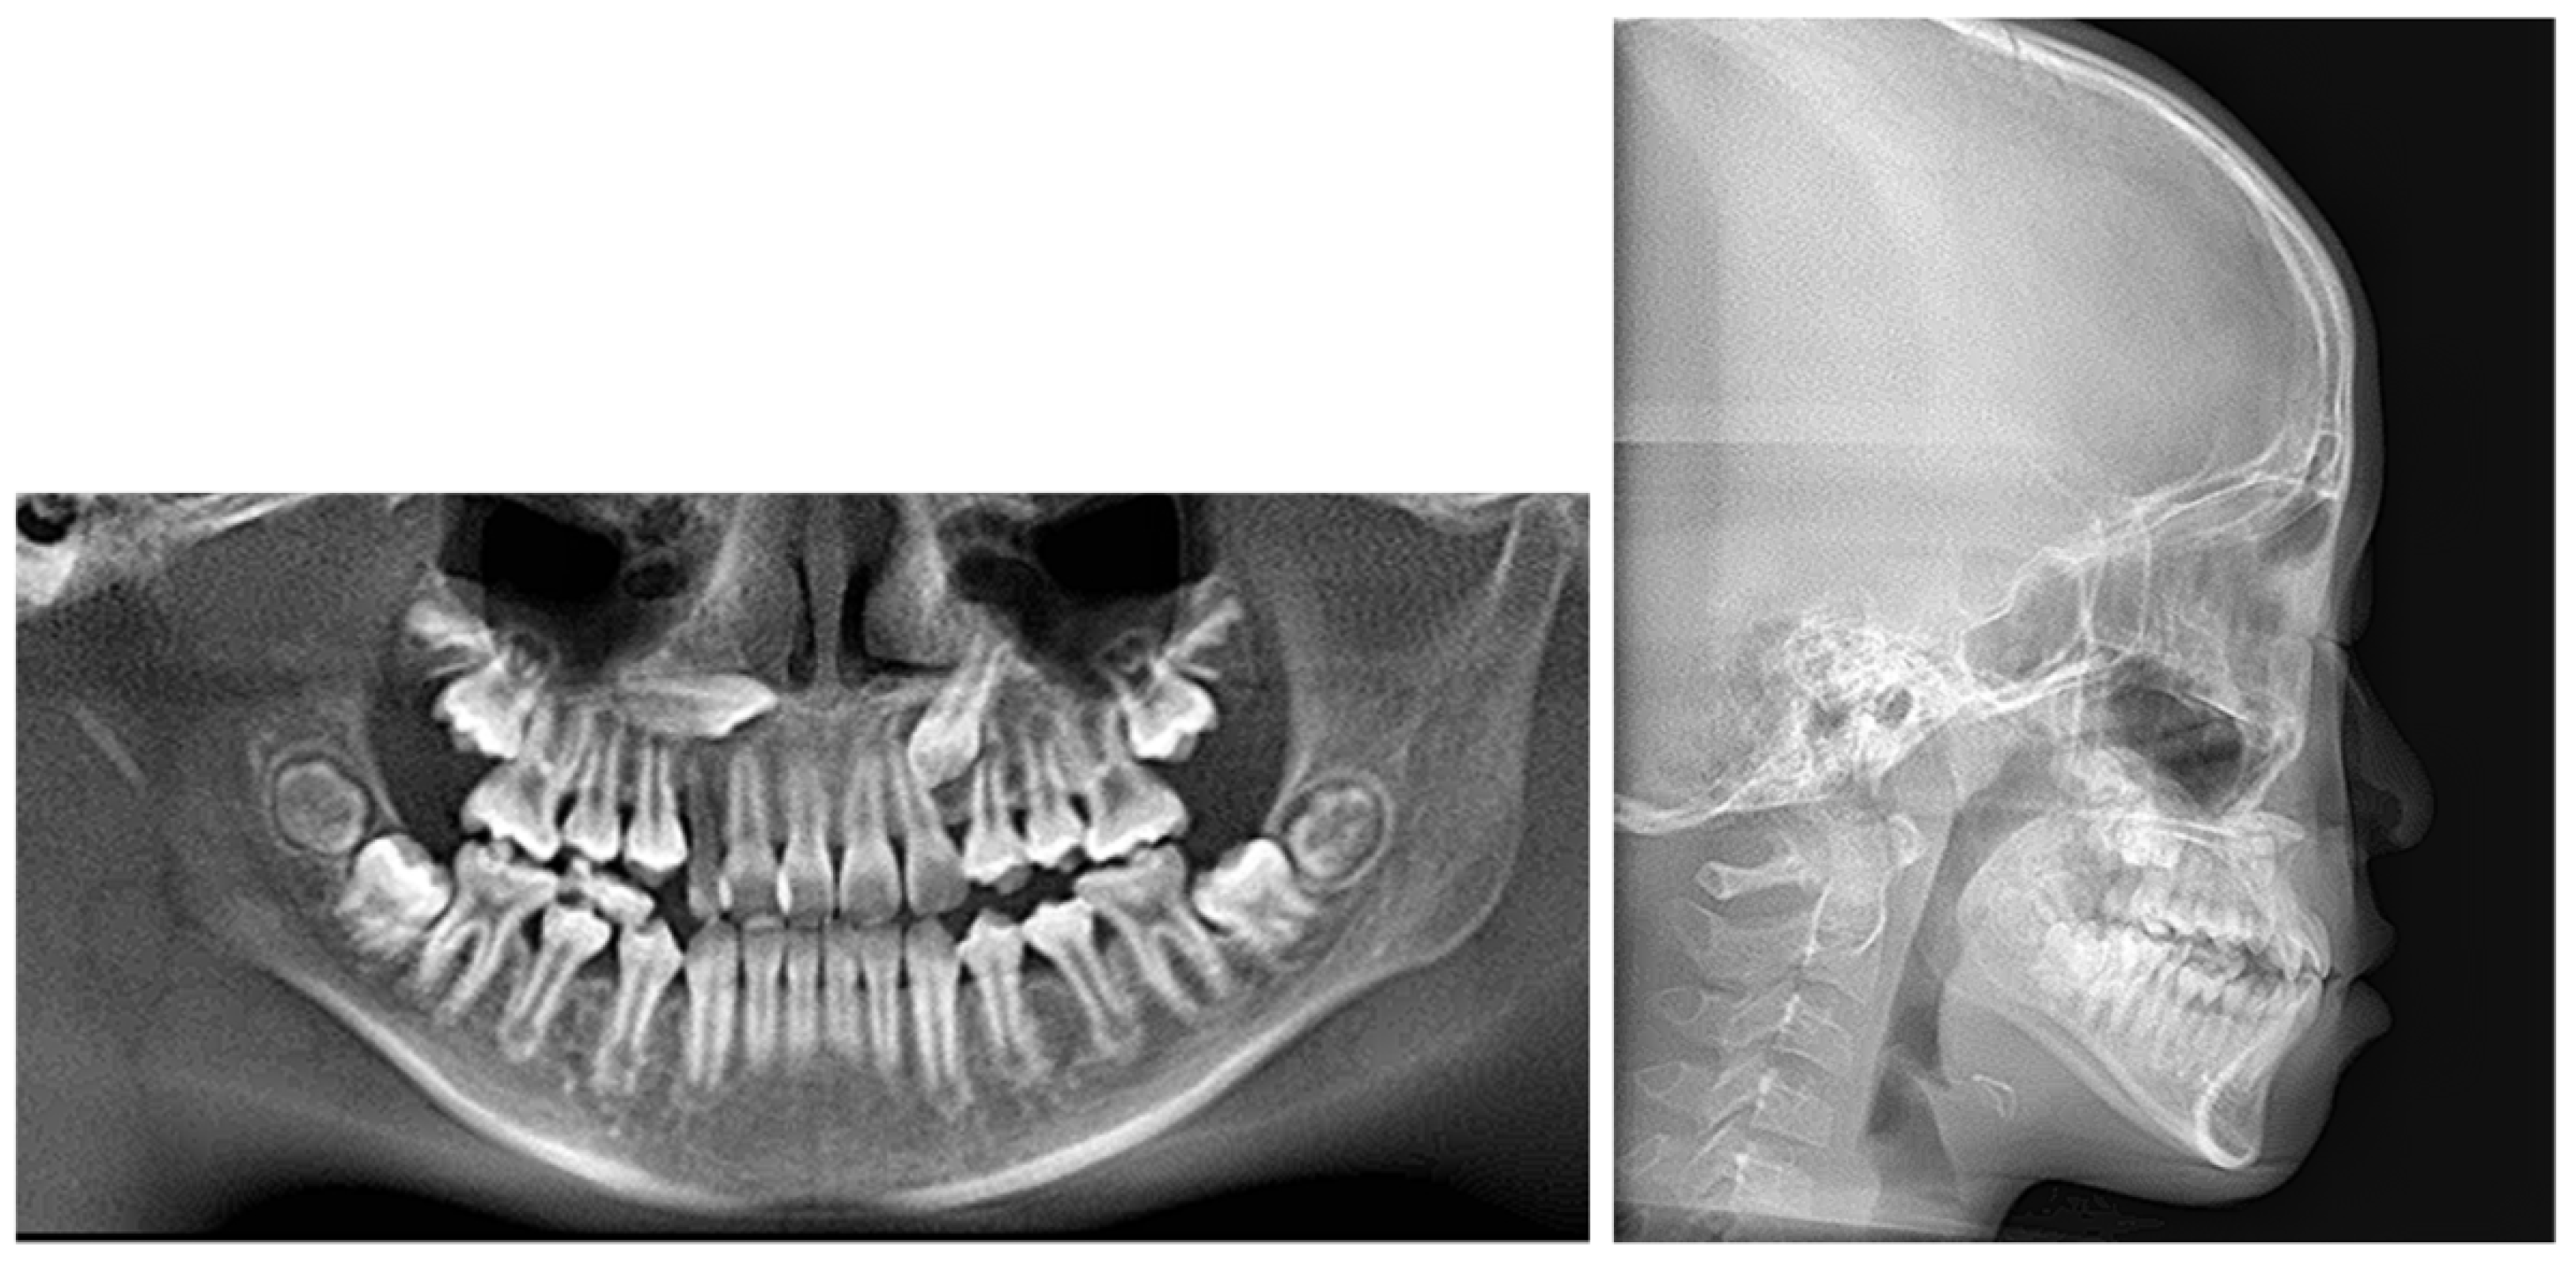

2.5. Treatment Results

3. Discussion